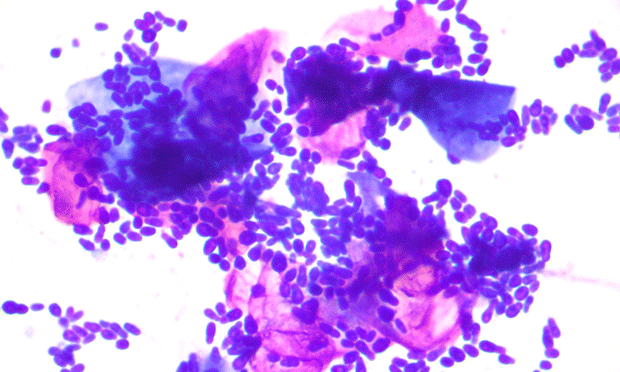

Ear infections under the microscope Franklin Vets

Ear Swabs Technique Interpretation in Vet Medicine